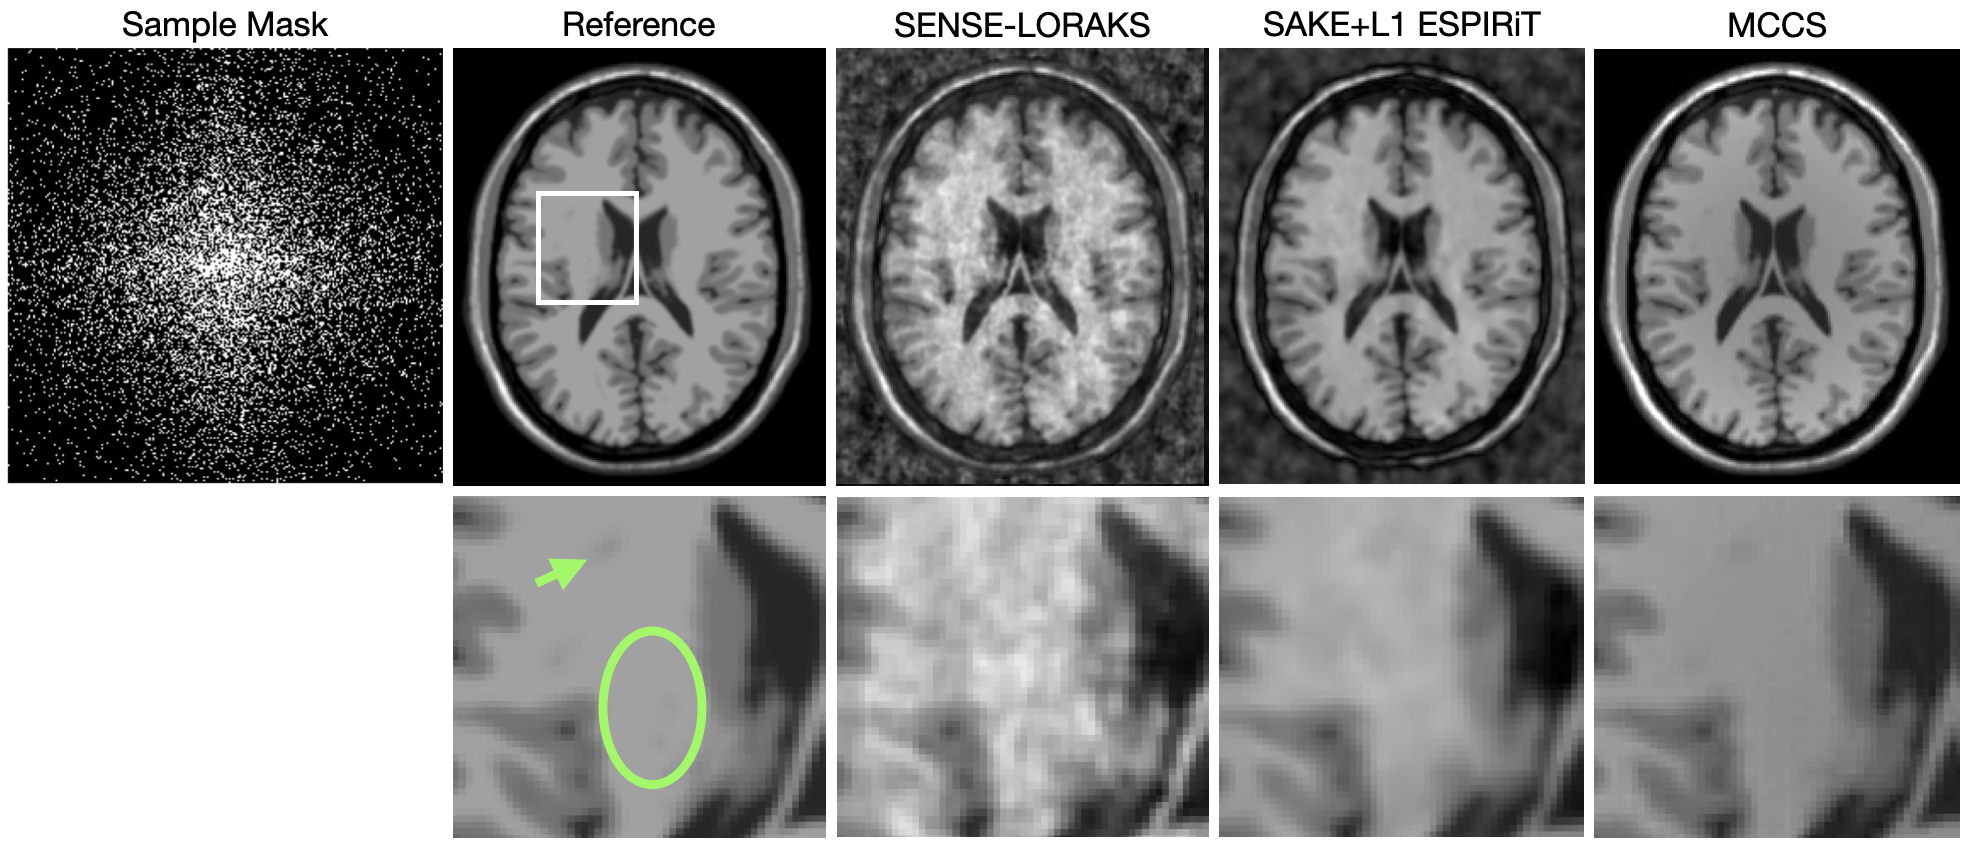

Figure 3 shows reconstructions of the brain simulations. MCCS is able to retain detail better than SAKE+L1 ESPIRiT; an example is depicted by the point indicated with the green arrow. MCCS is able to reduce noise better than SENSE LORAKS as shown in the region outside of the brain and the area enclosed by the green oval.

Figure 3: The left column shows the sample mask used for this data (white points represent samples that were collected). The top row shows the full field of view, the bottom row is zoomed into the white box overlaid on top of the reference image. The third, fourth, and fifth columns present reconstructions using SENSE-LORAKS, SAKE+L1 ESPIRiT, and MCCS with the sample mask shown, which is 20% of the data require for full sampling (that which satisfies the Nyquist-Shannon theorem). The green arrow points to a detail in the brain that is not apparent in the SENSE-LORAKS or SAKE+L1 ESPIRiT reconstruction but is visible in the MCCS reconstruction. The green ellipse encloses a region of high noise in the SENSE-LORAKS reconstruction but is not as noisy in the MCCS reconstruction.